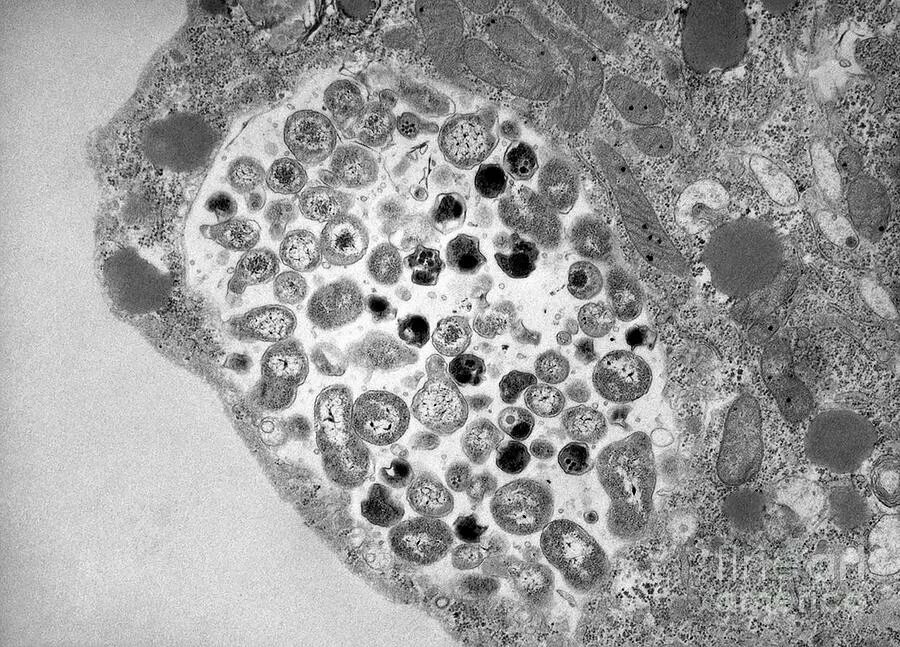

Хламидии под микроскопом